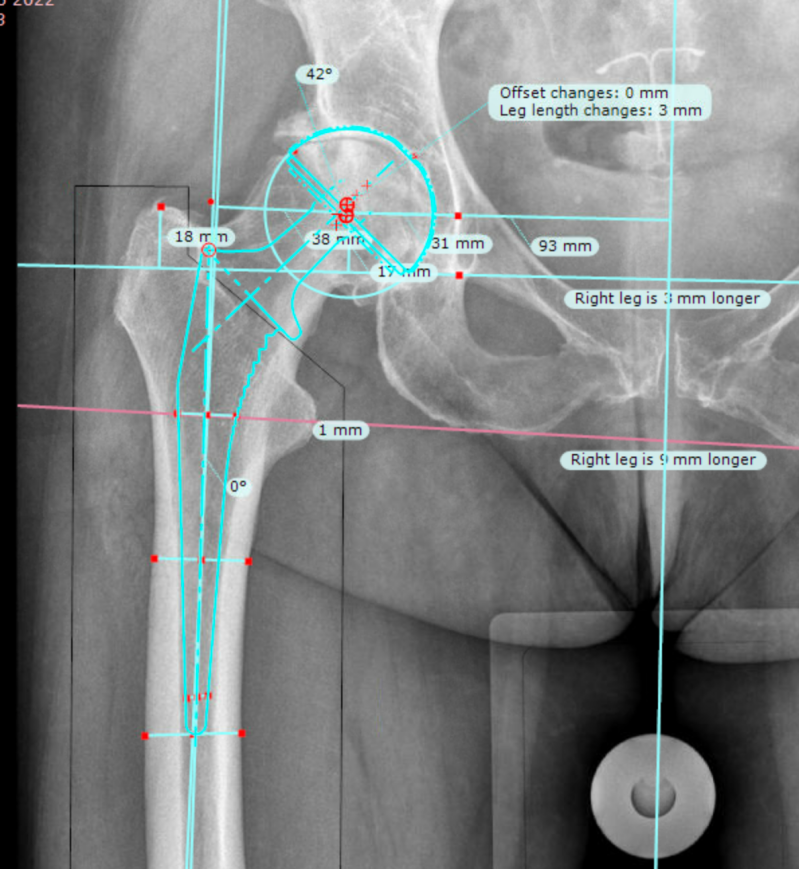

Met een computerprogram (Traumacad - Brainlab) maak ik een werktekening. Het precieze doel van de ingreep hangt af van het type heup, dwz de vormvariant. Je kunt de heup "nabouwen", maar soms op bepaalde punten aanpassen om de spierwerking te verbeteren . Het computer program kan de verschillende opties simuleren vóór de ingreep. Het draaipunt van de heup wordt gepland, dit is belangrijk voor de beenlengte en optimale werking van de spieren met de nieuwe heup. Ook de maten van de nieuwe heup worden bepaald.